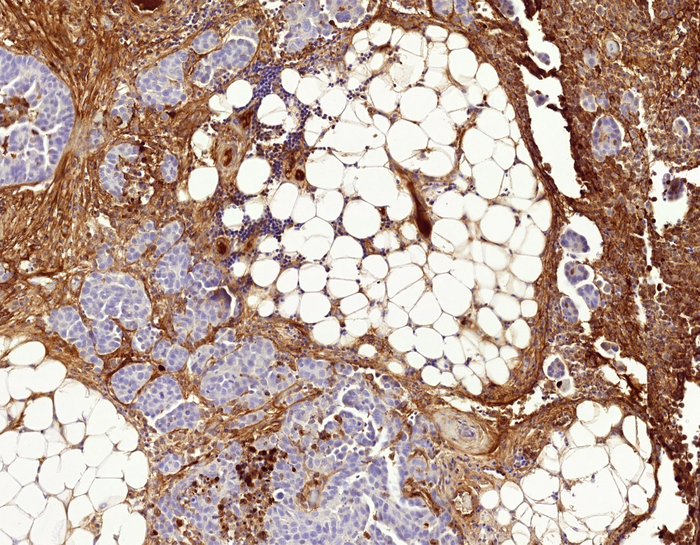

"A fibrotic network of proteins, known as the extracellular matrix or ECM, surrounds the cancer cells, particularly the most aggressive ones," says Lehti.

Fibrotic tissue is formed when the body tries to repair an injury. The fibrotic tissue, with the ECM network around the cancer cells, is mainly produced by normal connective tissue cells. But the cancer cells and connective tissue cells in the network can alter this tissue themselves.